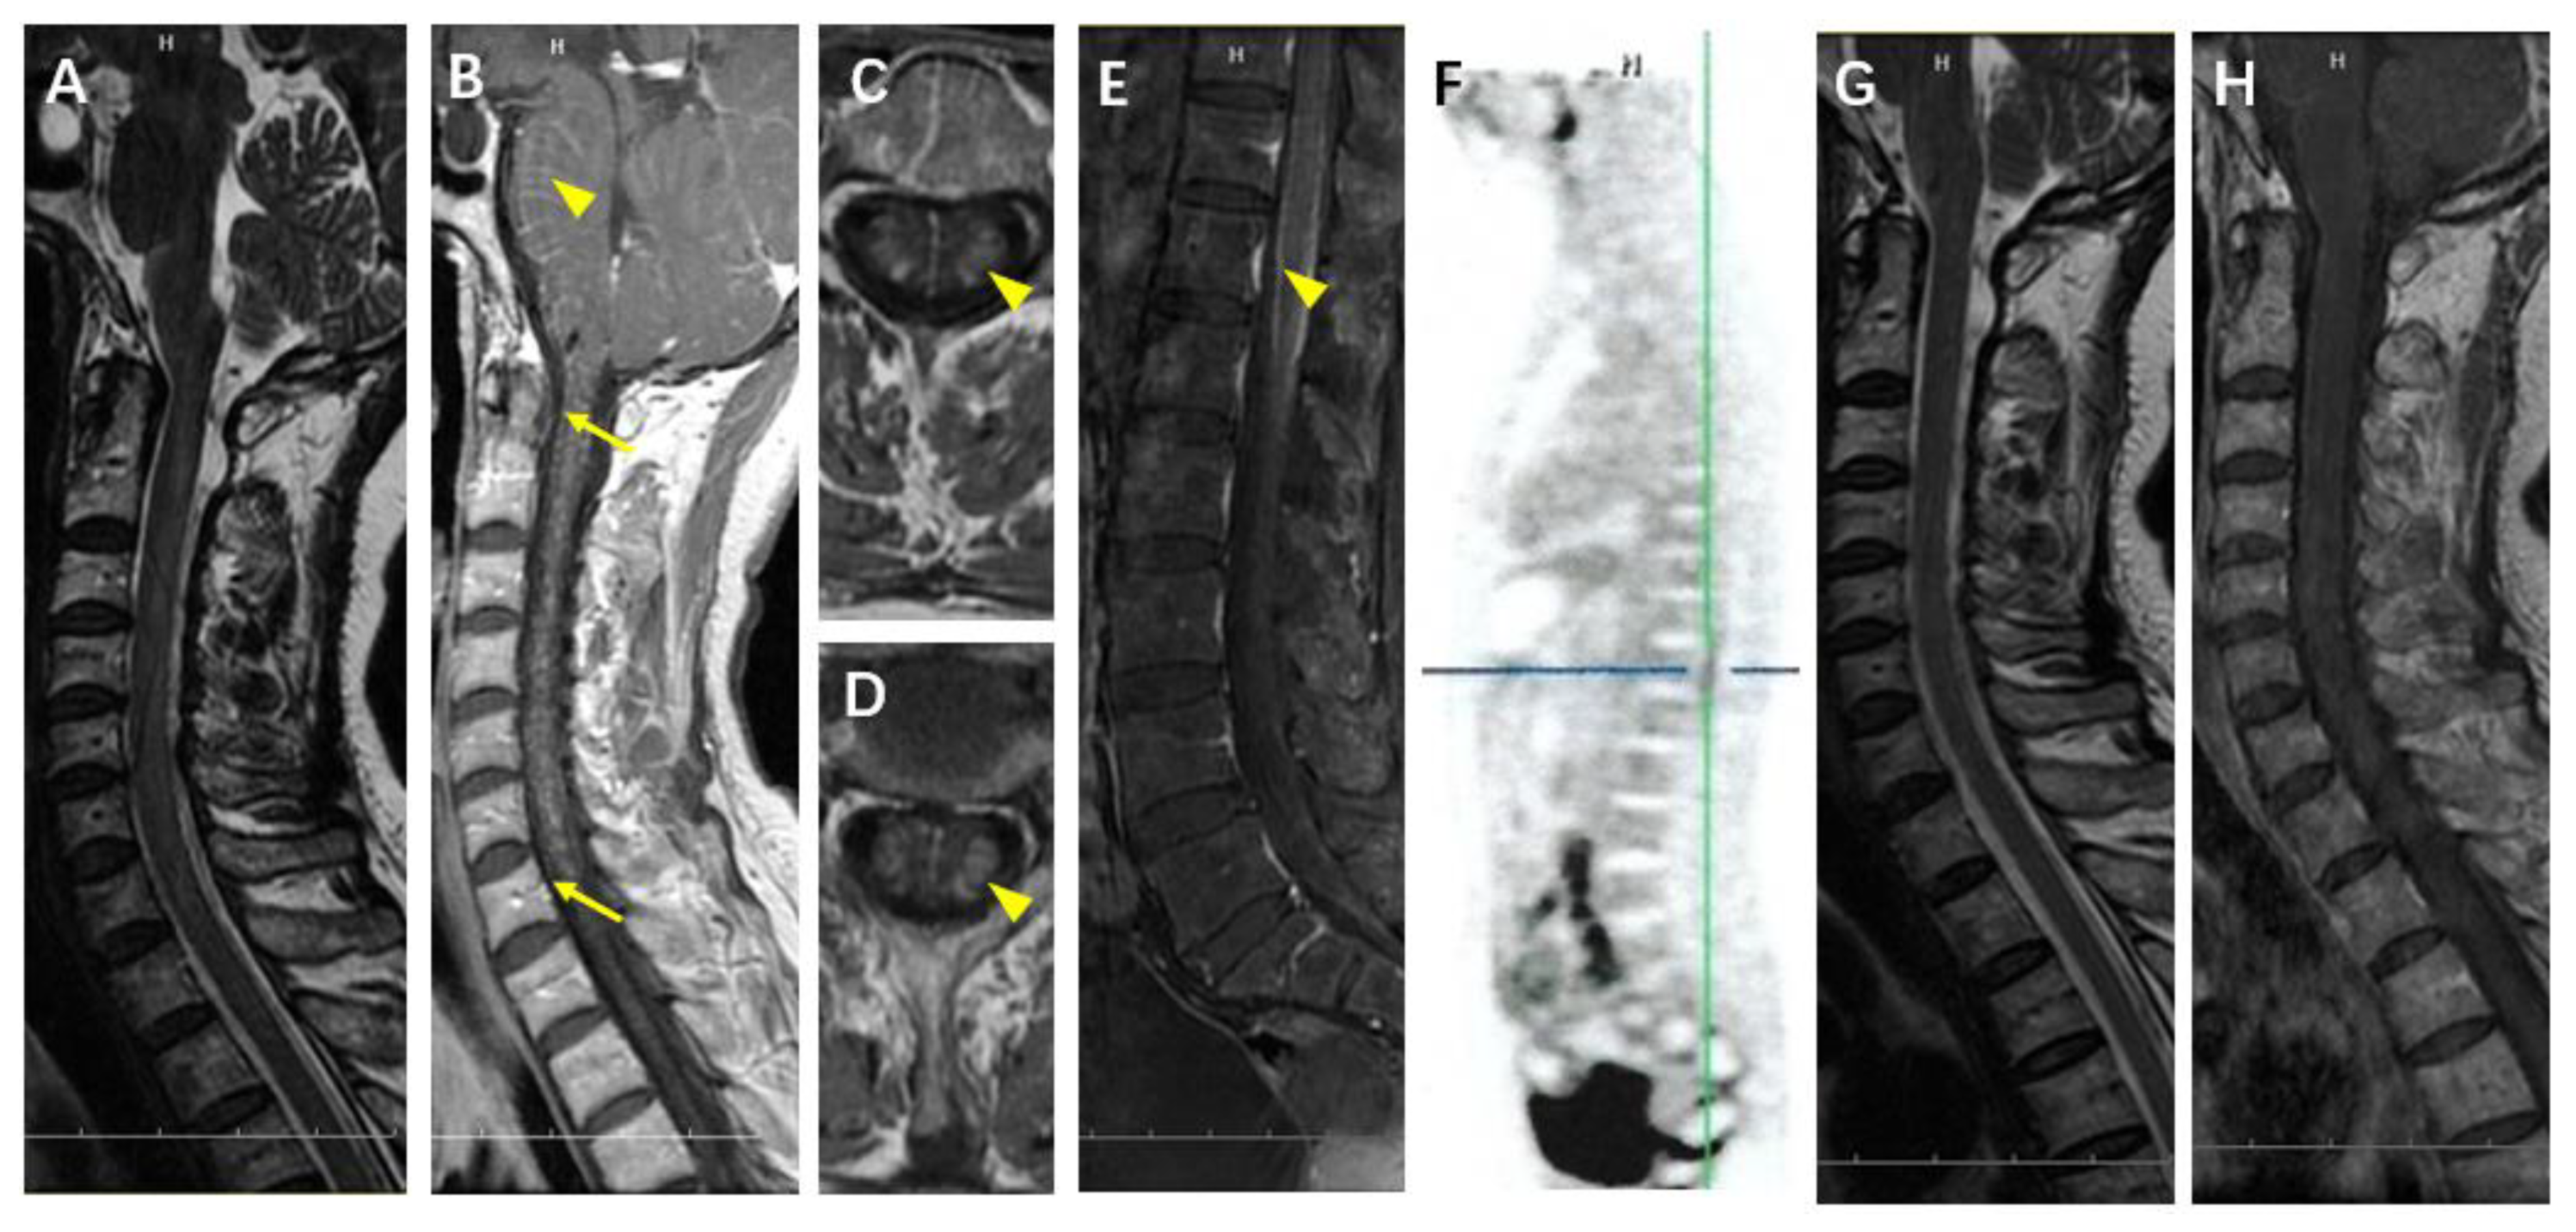

4.3. Case 5

4.4. Case 6